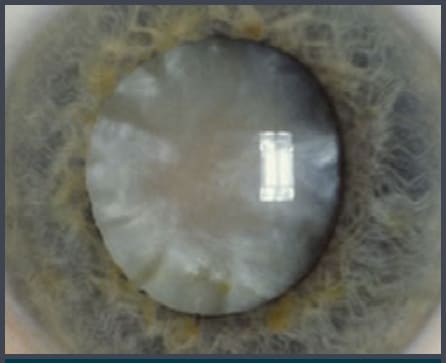

Fuchs' Dystrophy

The danger of Fuchs' dystrophy for cataract surgery patients is that this abnormality of the cornea's endothelial cells, recognizable on specular reflection as excrescences on the interior surface of Descemet's membrane, causes loss of vision through forward light scatter. This leads to reduced contrast acuity and even Snellen visual acuity when bumps are dense and central. More advanced Fuchs' dystrophy causes temporary or permanent endothelial decompensation following cataract surgery.

A careful slit lamp exam prior to cataract surgery should always include seeking abnormalities on specular reflection, including Fuchs' dystrophy. When in doubt, pachymetry and specular endothelial cell counts can help you stratify risk. Less than 1,000 cells per square millimeter and central pachymetry greater than 600 microns are warning signs of increased risk of decompensation.

In the past, the presence of Fuchs' dystrophy prompted us to delay cataract surgery in order to defer risk. Now we don't delay surgery, but rather intervene sooner to prevent endothelial damage from an overly sclerotic nuclear cataract. We find that patients with Fuchs' are less likely to decompensate if we remove the cataract earlier, when phacoemulsification requires less energy. Still, most corneas with at least moderate Fuchs' Dystrophy decompensate to at least some degree after surgery. It's wise to wait at least 2 to 3 months before determining that endothelial replacement surgery is necessary.